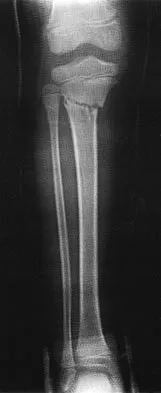

A 45-year-old male karate instructor sustained the injury shown in Figures 40a through 40c while practicing karate. The decision to proceed with surgery depends on which of the following factors?

Explanation

The most important criteria in determining the need for surgery following a nondisplaced or minimally displaced tibial plateau fracture is knee stability to varus/valgus stress. Soft-tissue injury noted on MRI may be addressed at a later time following fracture healing. This fracture pattern is amenable to nonsurgical management. Decisions regarding surgical intervention may be made up to 2 weeks after injury.